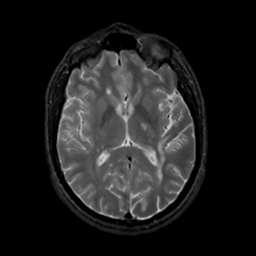

MR Study #7, March 24, 1991 -- Slice #26